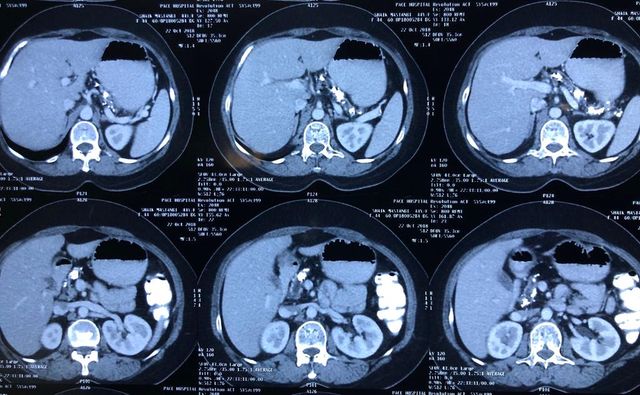

Challenging emergency during the COVID: Child’s A CLD with HUGE gastric varices uncontrolled

Child’s A CLD with HUGE gastric varices uncontrolled by Endoscopic glue and attempted EUS coiling. One salvage option would be TIPSS with balloon vascular occlusion but due to logistics we went for modified sugiura procedure. Splenectomy + Gastro esophageal devascularisation with anterior Gastrotomy and overseeing of gastric varices with pyloroplasty. Images show 1 CECT showing large gastric fundal varices. 2,3,4 Gastro Esophageal devasc 5, 6 Large fundal varices before and after oversewing. 7. Anterior gastrotomy 8. Pyloroplasty. Postoperative recovery was uneventful.